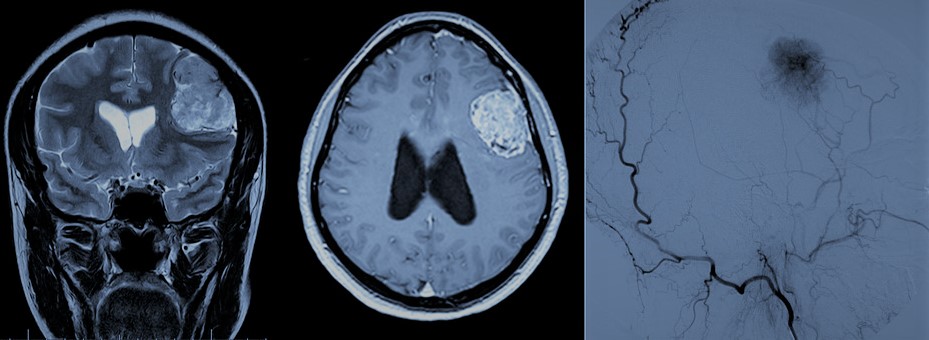

- Malformaciones arteriovenosas (MAV): Responsables de un 4-5% de las hemorragias subaracnoideas. Están representadas fundamentalmente por las MAV piales, caracterizadas por la presencia de ramas arteriales que dan lugar a un nido malformativo, compuesto por arteriolas y capilares aberrantes, que recibe sangre a alta presión y que drena a través de una o varias venas. Por lo general, se trata de lesiones complejas cuyo tratamiento va a estar condicionado por su tamaño, localización dentro del cerebro y características del drenaje venoso. En caso de que se diagnostiquen previo a su ruptura (generalmente debido a que pueden inducir crisis epilépticas) y midan menos de 3 centímetros, pueden ser tratadas con radiocirugía, si bien en estos casos el efecto del tratamiento se demora unos 2 años. La cirugía por su parte constituye el tratamiento estándar de estas lesiones. Puede tener lugar, al igual que los aneurismas, de forma previa a la ruptura o bien tras producirse ésta. Previo a la cirugía debe considerarse la posibilidad de la embolización de la lesión.